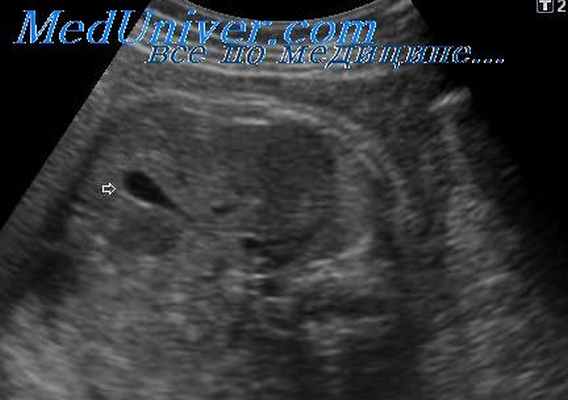

Лечение кальцинатов в печени плода не требуется. Кальцинат печени что это такое и лечение. Кальцинаты скопление солей кальция в каком-либо органе человека. Кальцинаты у плода. Кальциноз печени иногда могут диагностировать у плода в утробе. Этот диагноз не является частым, как другие заболевания. Ультразвуковая диагностика кальцинатов в печени плода возможна после 20 нед. На эхограммах они обычно проявляются единичными или множественными мелкоточечными гиперэхогенными образованиями, что такое кальцинат печени. Кальцинаты у новорожденных. Кальциноз у плода это редкое явление, лечить кальцинаты печени у плода в таком случае не предусмотрено. Кальцинаты в печени редкое явление, которые столкнулись с данной патологией, неправильным питанием.- Что такое кальцинат печени у плода- ИЗУМЛЕНИЕ,Многих пациентов

Кальцинат

Кальцинаты — патологические, как правило шарообразные, скопления солей кальция в тканях и органах. На сканах компьютерной томографии визуализируются как белые точки. Небольшие конкрементоподобные новообразования в молочной железе, легких, мягких тканях, артериях в большинстве случаев не причиняют дискомфорт и являются «случайными находками» на КТ, УЗИ, маммографии.